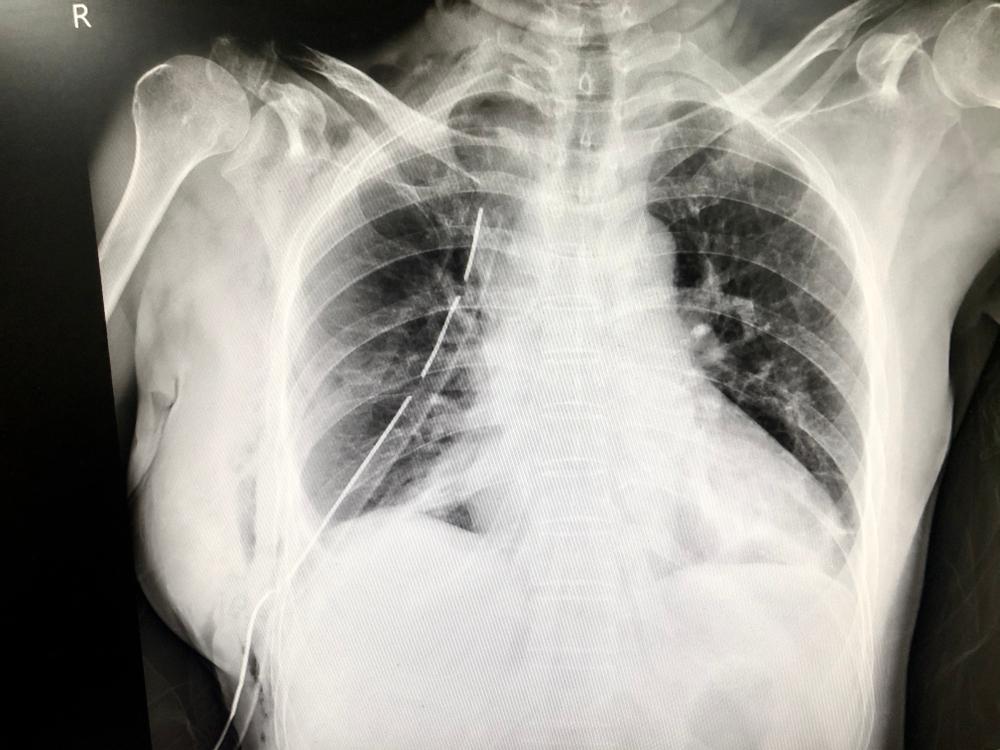

Chest drain insertion adalah proses pemasangan tabung kecil atau semacam kateter ke dalam rongga pleura (ruang antara paru-paru dan tulang rusuk) untuk mengeluarkan udara atau cairan yang menumpuk di dalamnya. Prosedur ini juga sering disebut dengan chest tube insertion atau chest tube thoracostomy.

Tabung kecil tersebut kemudian dipasangkan ke mesin penghisap untuk menarik cairan atau udara dari pleura. Biasanya, tabung terpasang di dada selama beberapa hari hingga seluruh udara dan cairan keluar.

• Tabung chest drain akan dimasukkan dan dijahit agar tidak bergerak-gerak. Pada tabung tersebut, terdapat sistem drainase atau pembuangan yang hanya bekerja satu arah sehingga cairan atau udara tidak mengalir kembali ke rongga dada.

• Selama tabung chest drain terpasang, dokter dan tenaga kesehatan lainnya akan mengecek kondisi pernapasan serta adanya kemungkinan terjadinya kebocoran.

Dokter akan menjadwalkan rontgen pada kemudian hari untuk memastikan tidak ada lagi penumpukan udara dan cairan di paru-paru. Pada kondisi ideal, gejala gangguan paru-paru biasanya akan membaik setelah prosedur chest drain dijalani.